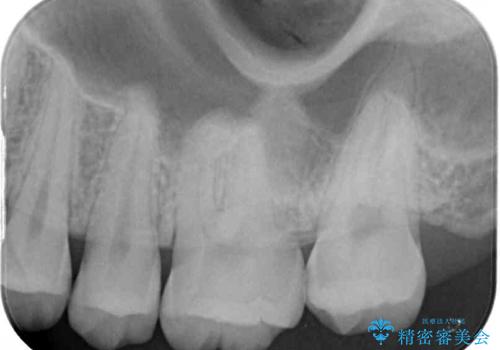

- 奥歯にフロスが引っかかるようになり、虫歯ではないかとのことで来院された患者様です。

レントゲン写真より、1番奥の歯に虫歯があることが分かりました。

奥で目立たないことから、虫歯の再発リスクが最も低く、咬合力による歯への負担も少ないゴールドインレー(PGAインレー、白金加金インレー)にて修復治療をすることとしました。